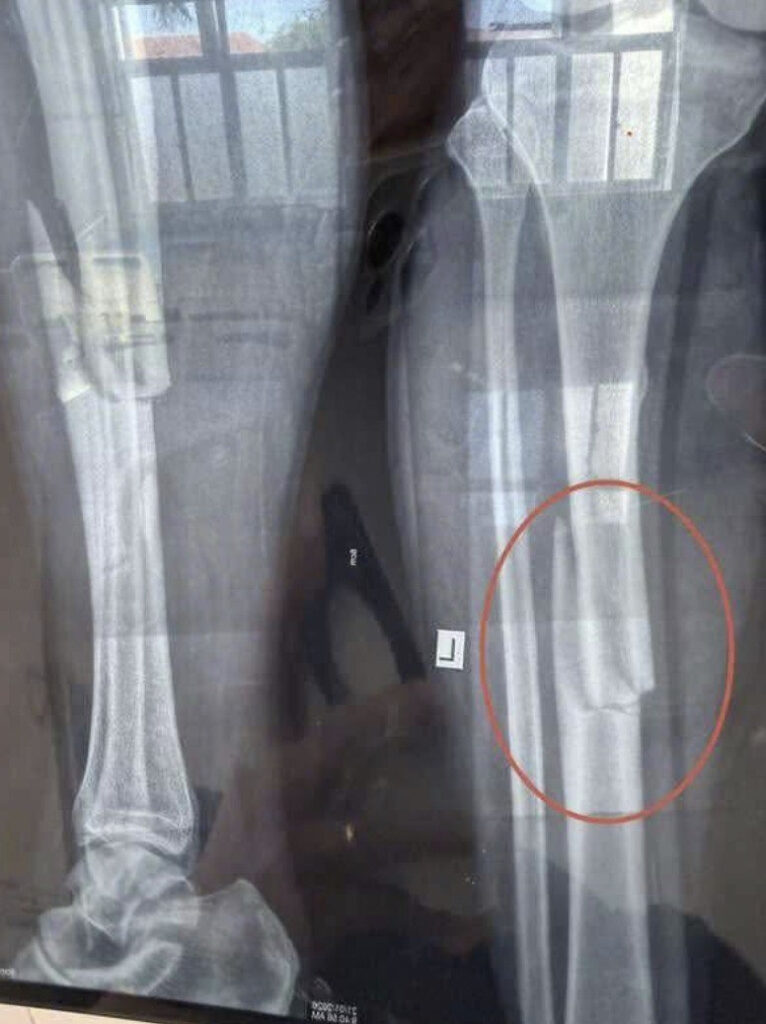

Phước Đông – Tây Ninh: TNLĐ trong lúc làm việc khiến nam thanh niên gãy chân